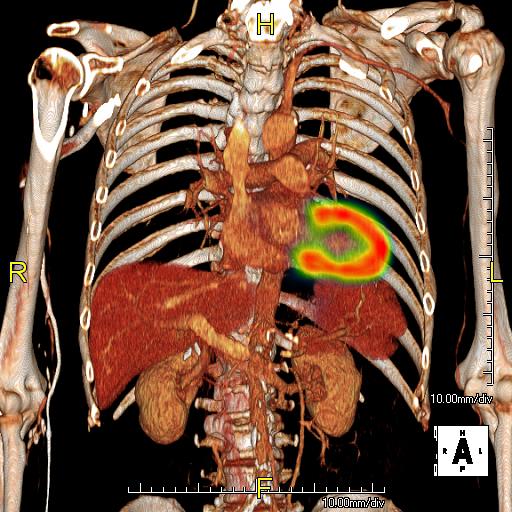

The C-NIR group is dedicated to performing Molecular Imaging Research in humans with state of the art PET/CT and SPECT/CT capabilities. Our imaging scanners are run by highly trained and qualified Nuclear Medicine and CT certified technologists. We also have imaging science experts to provide additional help on diagnosis, image reconstruction, co-registration, tracer kinetic modeling, and quantifications.

A "research study" PET/CT or SPECT/CT consist of any PET/CT or SPECT/CT performed in humans that differs in some fashion from the standard clinical protocol. The deviation from the standard clinical protocol could be (but not limited to): the radiopharmaceutical, the acquisition protocol, the reconstruction or the biodistribution time.